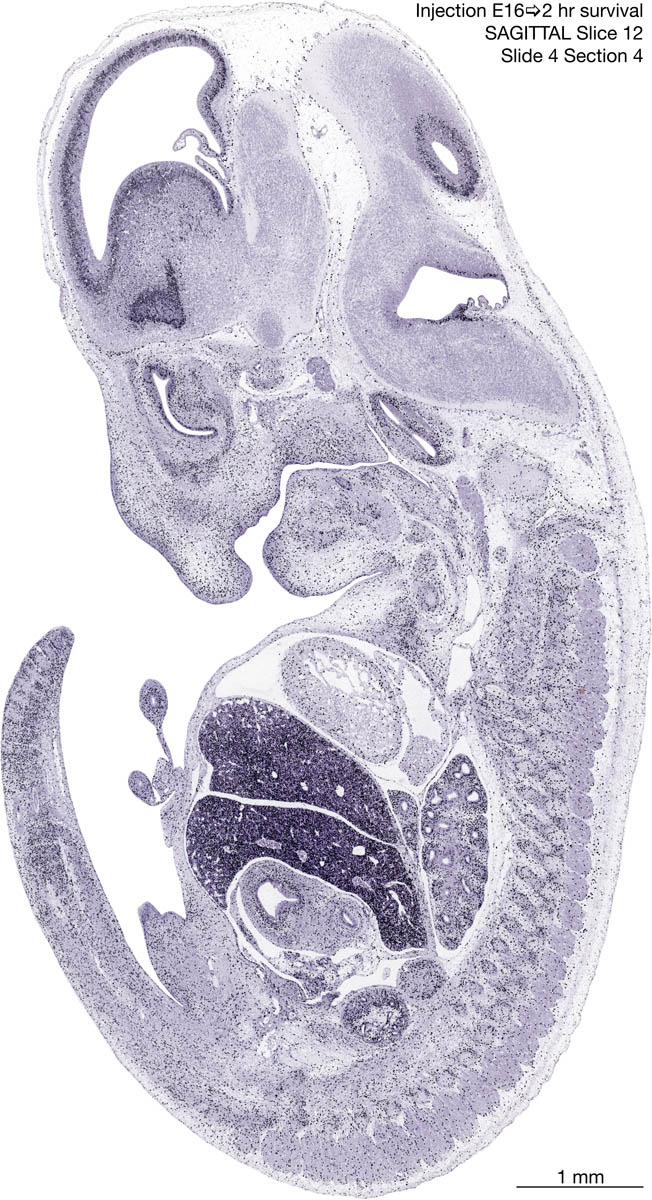

E16 2hr Survival Archived Images-Sagittal The following images are from a paraffin-embedded sagittally-sectioned E16 rat embryo exposed to tritiated thymidine 2 hours before death. Download: Large | High Res Download: Large | High Res Download: Large | High Res Download: Large | High Res Download: Large | High Res Download: Large | High Res Download: Large | High Res Download: Large | High Res Download: Large | High Res Download: Large | High Res Download: Large | High Res Download: Large | High Res Download: Large | High Res Download: Large | High Res Download: Large | High Res Download: Large | High Res Download: Large | High Res Download: Large | High Res Download: Large | High Res Download: Large | High Res Download: Large | High Res Download: Large | High Res Download: Large | High Res Download: Large | High Res Download: Large | High Res Download: Large | High Res Download: Large | High Res Download: Large | High Res Download: Large | High Res Download: Large | High Res Download: Large | High Res Download: Large | High Res Download: Large | High Res